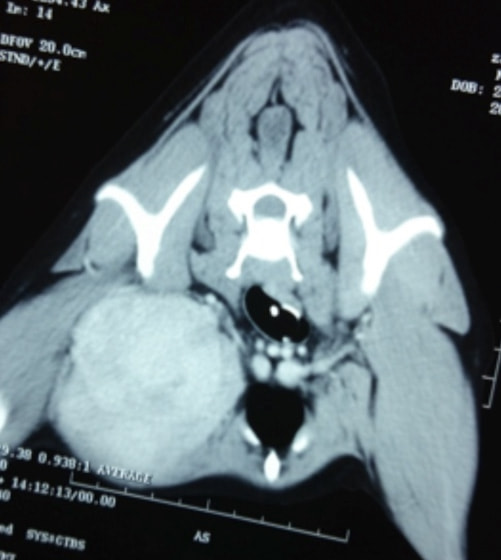

症例:腋窩部の軟部組織肉腫 ウェルシュ・コーギー 11歳 去勢オス

CT写真

右前肢の破行および疼痛を主訴に来院。消炎剤による内科療法にて疼痛の改善はあるものの、破行の継続および神経反射の低下が認められたため、MRIおよびCT検査を実施。

CT所見:右腋窩部に腫瘤の形成を確認

腫瘤の針吸引生検を行い、細胞診の結果腫瘍が疑われたため、腫瘤の摘出手術を実施した。CT検査にて、腫瘤は深部まで及び周辺組織を巻き込んでいるのが確認されていたことから、完全摘出のため同時に右前肢の断脚術を行った。